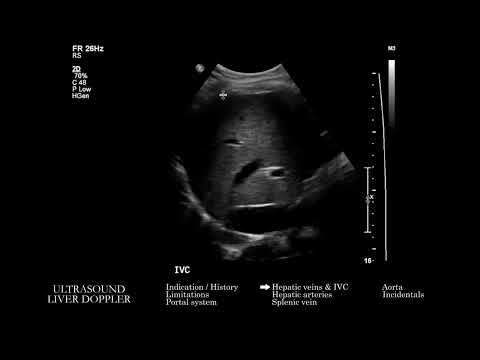

Допплерография сосудов печени. Часть 1.

Лекция для врачей ультразвуковой диагностики. Запись 25. 09. 2018 г.